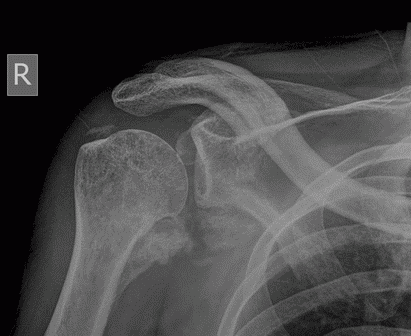

男,三十岁,多处外伤性骨折术后两月余。

骨化性肌炎:原因不明,多于外伤有关。好发于青年男性,多位于受伤部位的四肢深部组织如股四头肌、股内收肌、上臂肌及肘部肌群内,但不局限于肌肉。

临床上多有外伤史,及全身疾患如截瘫、昏迷等。早期局部肿胀、疼痛,可扪及包块,邻近关节活动受限。病理:早期为局部软组织水肿、变性、坏死、肌纤维断裂及原始间叶细胞增生形成肿块,之后肿块变硬,最外层形成成熟的纤维组织和骨组织,肿块不侵犯骨组织,但可与骨皮质相连。

影像表现为初期患处局限性肿胀,肌间隙模糊,密度增高,之后出现絮状钙化影及毛糙不整的网状致密影,邻近骨质可有骨膜反应;中期肿块内出现条状或层状钙化影,边缘部位出现致密骨。后期肿块缩小,与邻骨间以透亮带相隔或紧密相连,肿块内出现高密度钙化及骨结构形成,骨化影大部分沿肌束走行,是其重要鉴别点。需与下列疾病鉴别,1.骨外软组织骨肉瘤 2.骨外软骨肉瘤  3.皮质旁骨肉瘤 4.骨间膜钙化 5.进行性骨化性肌炎及软组织的其他钙化性疾病。

骨旁软组织内见广泛斑片条状密度增高影,考虑外伤性骨化性肌炎。